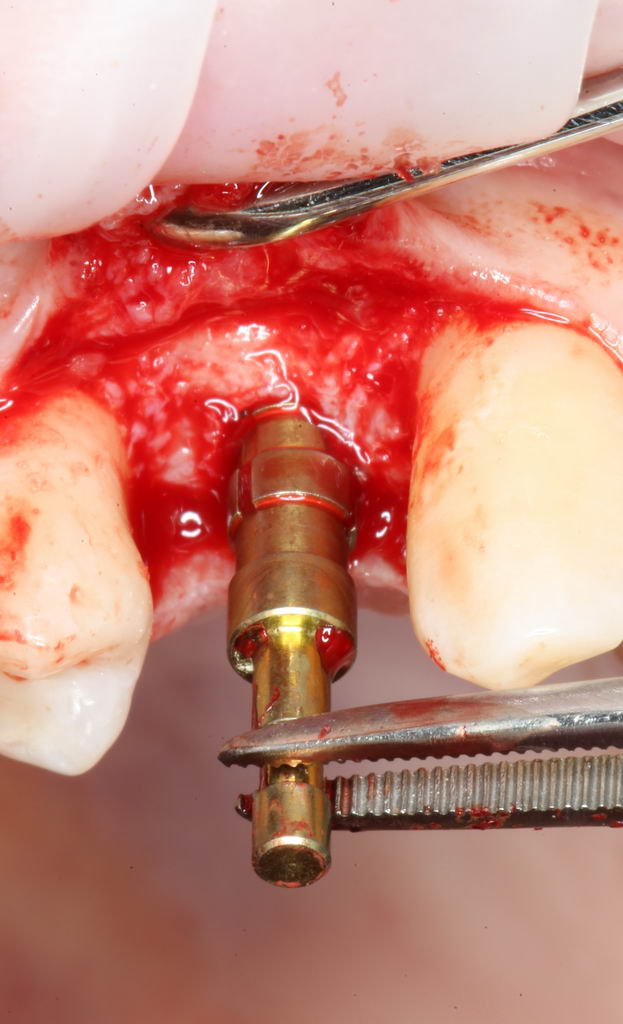

Имплантат нужного размера (3.8х11 мм) фиксируется на гексагональном ключе, после чего устанавливается в подготовленную лунку:

Превышение усилия — это повышение нагрузки (читай, излишняя травма) на костную ткань вокруг имплантата. Что, в свою очередь, ведёт к периимплантиту или отторжению. Вот почему важно контролировать и регистрировать крутящий момент в процессе установки.

Как видите, в нашем случае он не превышает 25 Нсм — оптимально даже для немедленной нагрузки. Это значит, что необходимые параметры имплантации выдержаны правильно.

Еще раз проверим положение имплантата:

Учитывая то, что на нём уже установлен временный абатмент TempBase, сделать это очень просто. Фактически, сейчас мы с Вами видим картинку, которую увидит ортопед перед установкой коронки. Это очень удобно.

Больше нам абатмент TempBase не нужен, мы его убираем:

Без абатмента можно оценить позиционирование имплантата по глубине погружения. Напомню, что XiVE — это субгингивальная имплантационная система, поэтому ортопедическая платформа имплантата должна находиться на уровне костной ткани. Что и было выполнено в нашем случае.